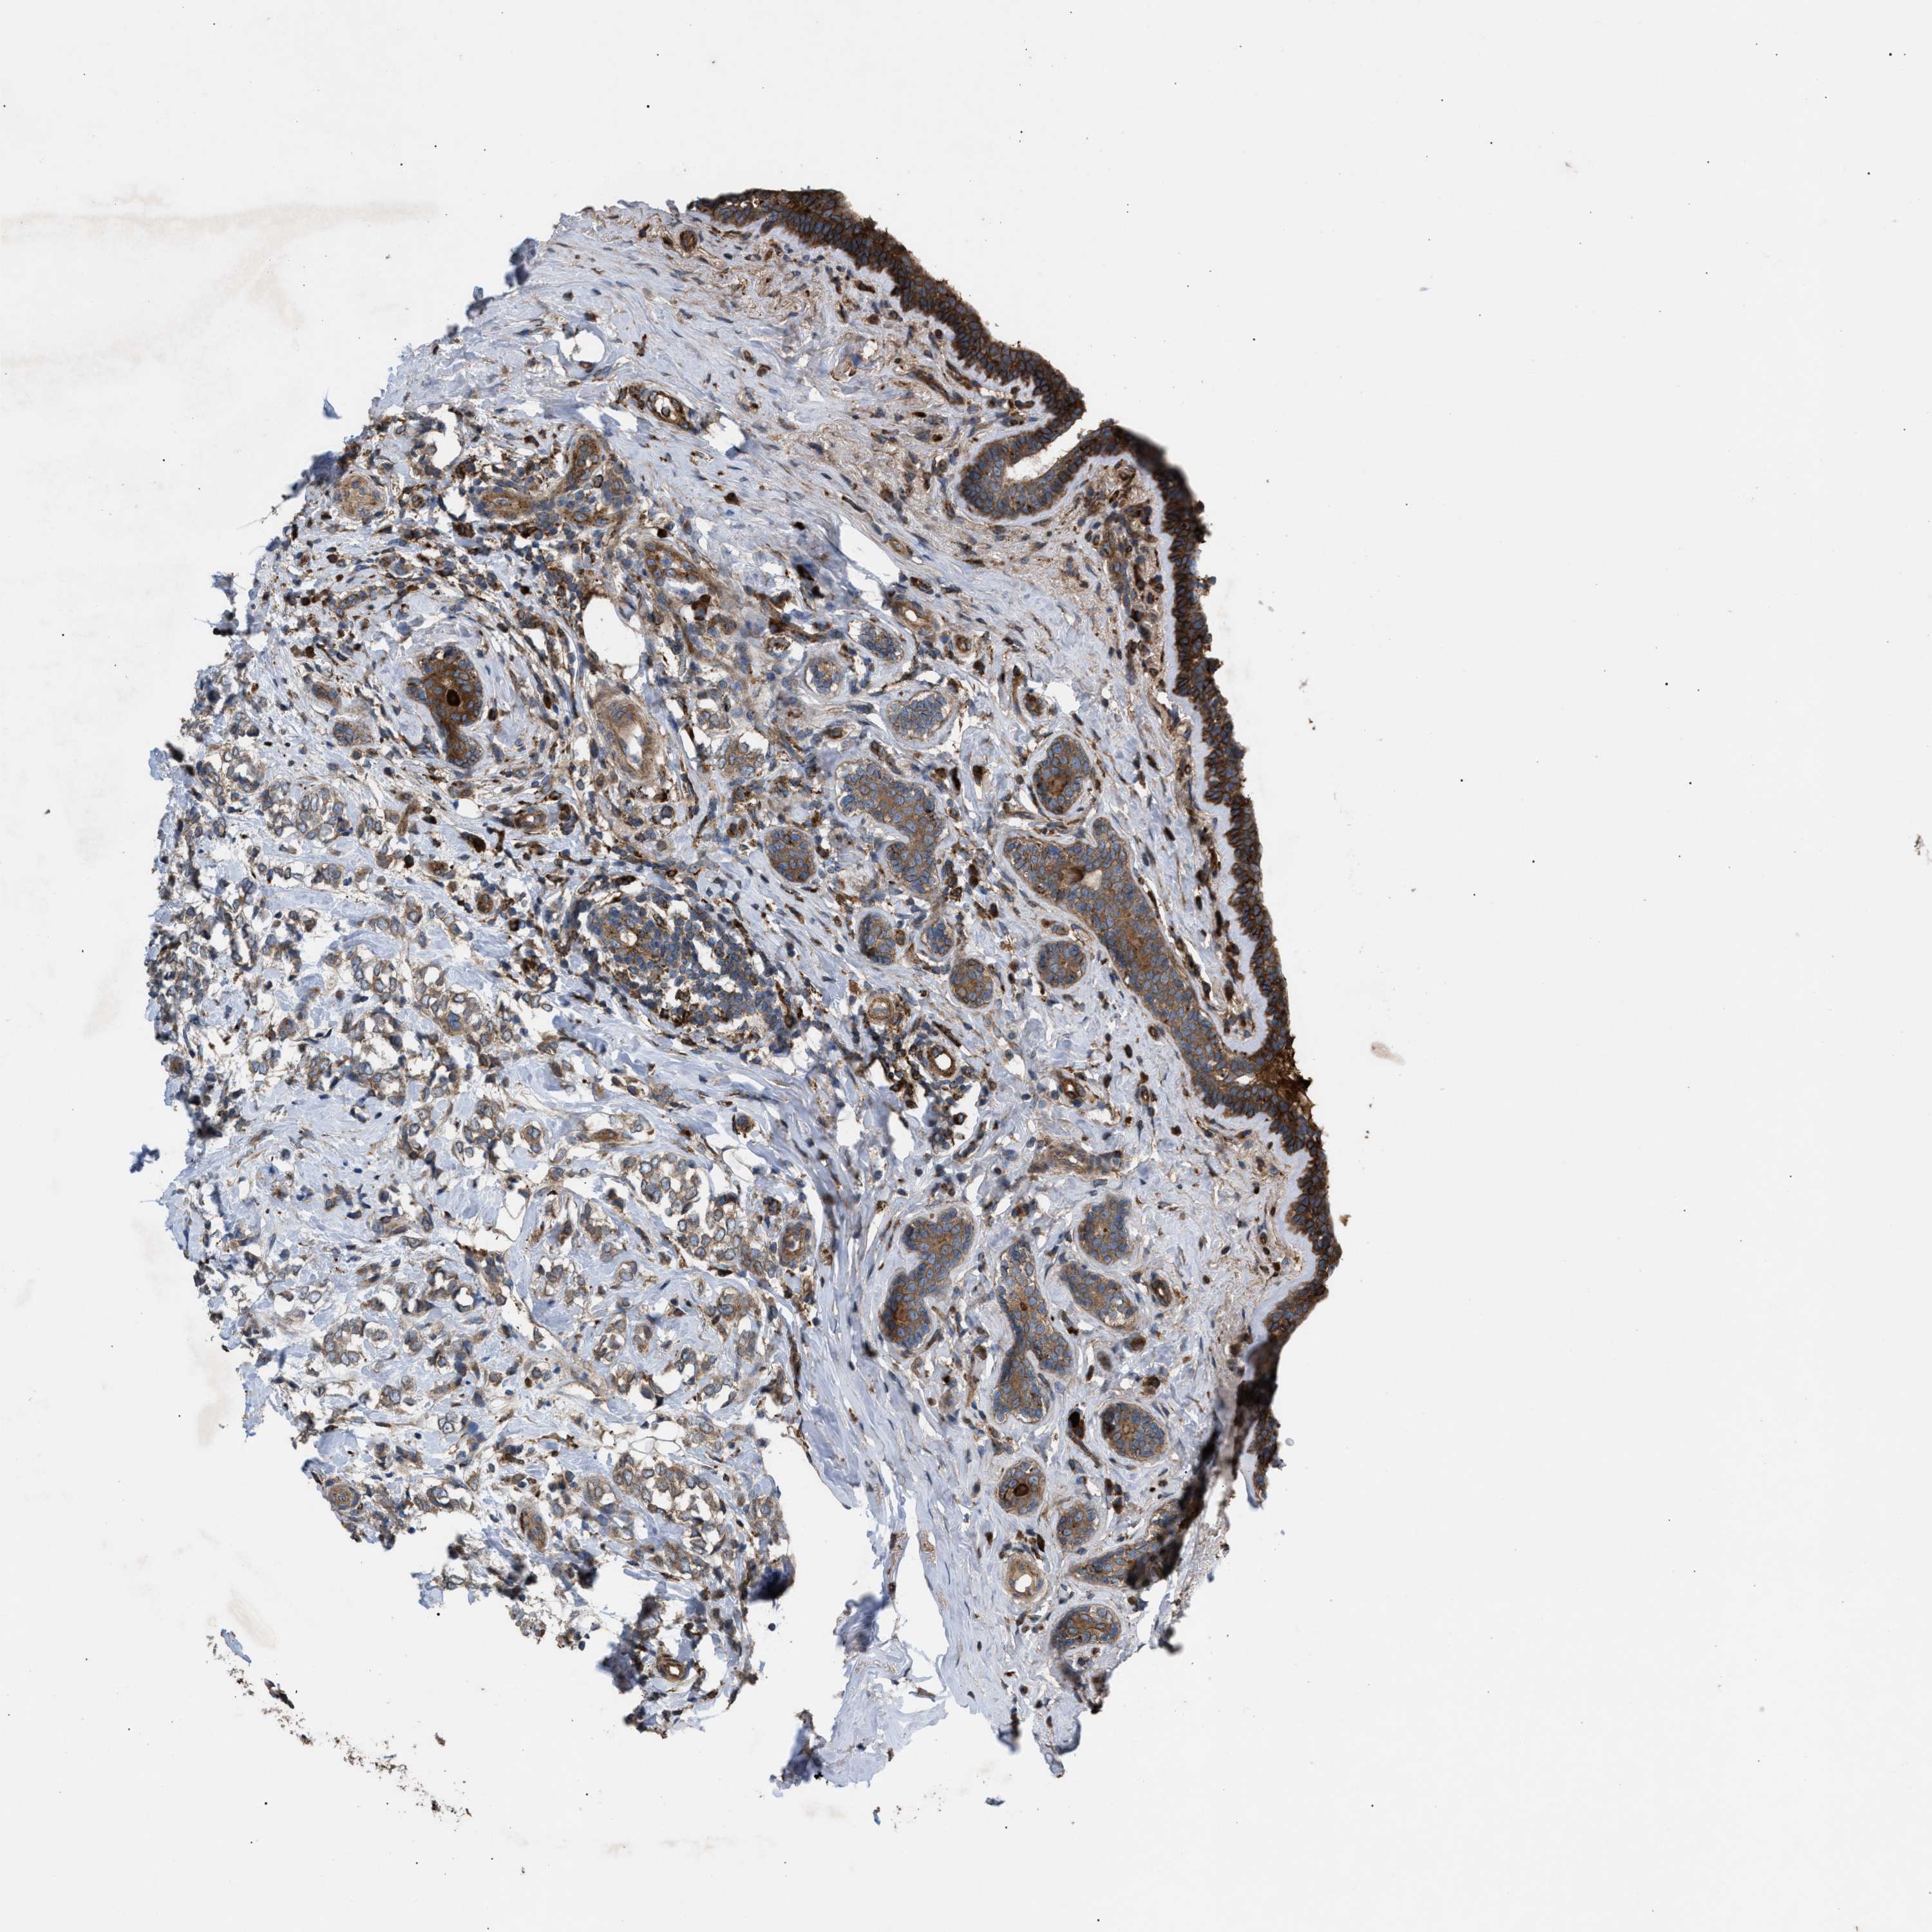

CANCER BREAST CANCER Show tissue menu

BRCA TCGA BRCA VALIDATION PROTEIN EXPRESSION

ANTIBODIES

AND

VALIDATION